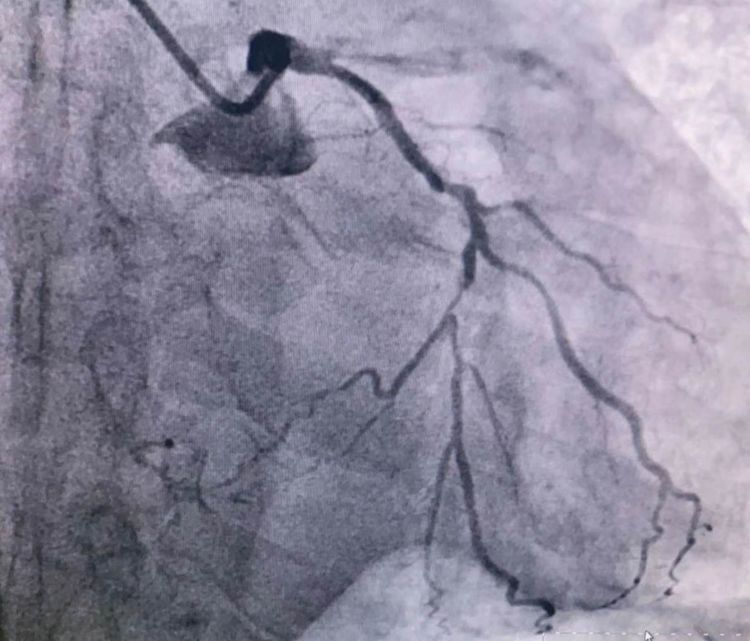

患者前降支、右冠100%闭塞,LCX中段60%狭窄。命悬一线,手术台上持续胸痛。和患者家属及时沟通后,决定行PTCA术。血压低至60/40mmHg,在主动脉内球囊反博的支持下紧急行PCI术。轨道很快建立,导丝也及时通过病变血管,噩梦来了,患者发生室颤了。在吴栋梁院长的指挥下,李阳主任和心脏团队的成员共同努力下,除颤、冠脉内溶栓、多个球囊轮流上阵,患者病情平稳了,罪犯血管及时开通,血流恢复三级血流。平安下台,准备择日再处理冠脉情况。